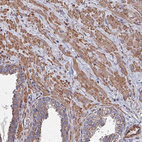

Immunohistochemical staining of human duodenum shows strong cytoplasmic positivity in glandular cells.